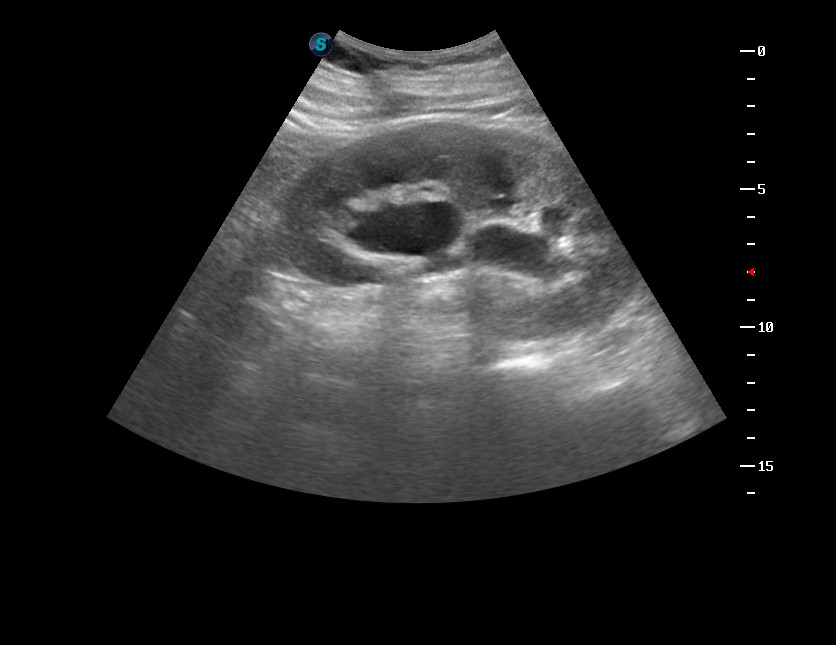

Кисты почечного синуса, иммитирующие гидронефроз

Женщина 48 лет

Левая почка.

Ну на 100% я не уверена и в таком случае, думаю, написала бы эти 2 варианта под вопросом, а там уже дело экскреторной урографии. Но мне, кажется, что в данном случае, при гидронефрозе лоханка была бы побольше, да и форма жидкостных образований (их медиальная часть) меня как-то к кистам больше склоняют.

Сделана МРТ - кисты.